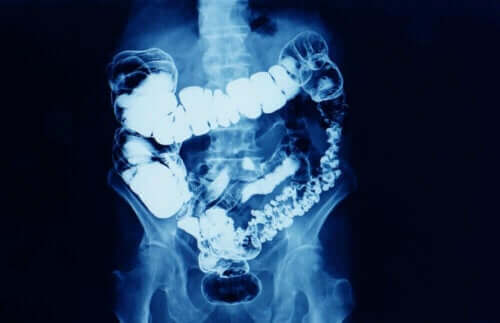

Over het algemeen is constipatie wanneer de frequentie van het passeren van ontlasting afneemt. Constipatie is een symptoom dat betekent dat de darmtransit om de een of andere reden wordt verminderd.

Constipatie treft meer vrouwen dan mannen, vooral vrouwen tussen de 20 en 35 jaar en na de leeftijd van 60 jaar. Afhankelijk van hoe lang het duurt, kan constipatie in twee typen worden ingedeeld: